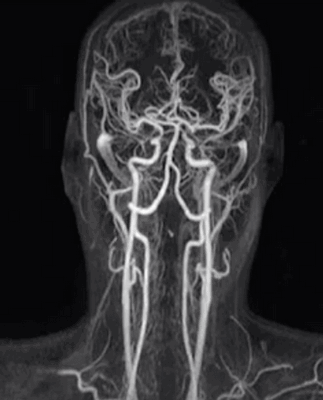

МР-ангиография сосудов головы и шеи позволяет на ранних этапах выявить развитие состояний, способных привести к острым или хроническим нарушениям мозгового кровообращения и атрофическим изменениям. Исследование вен и артерий необходимо для выявления:

![МР-ангиография артерий головы и шеи]()

МР-ангиография артерий головы и шеи